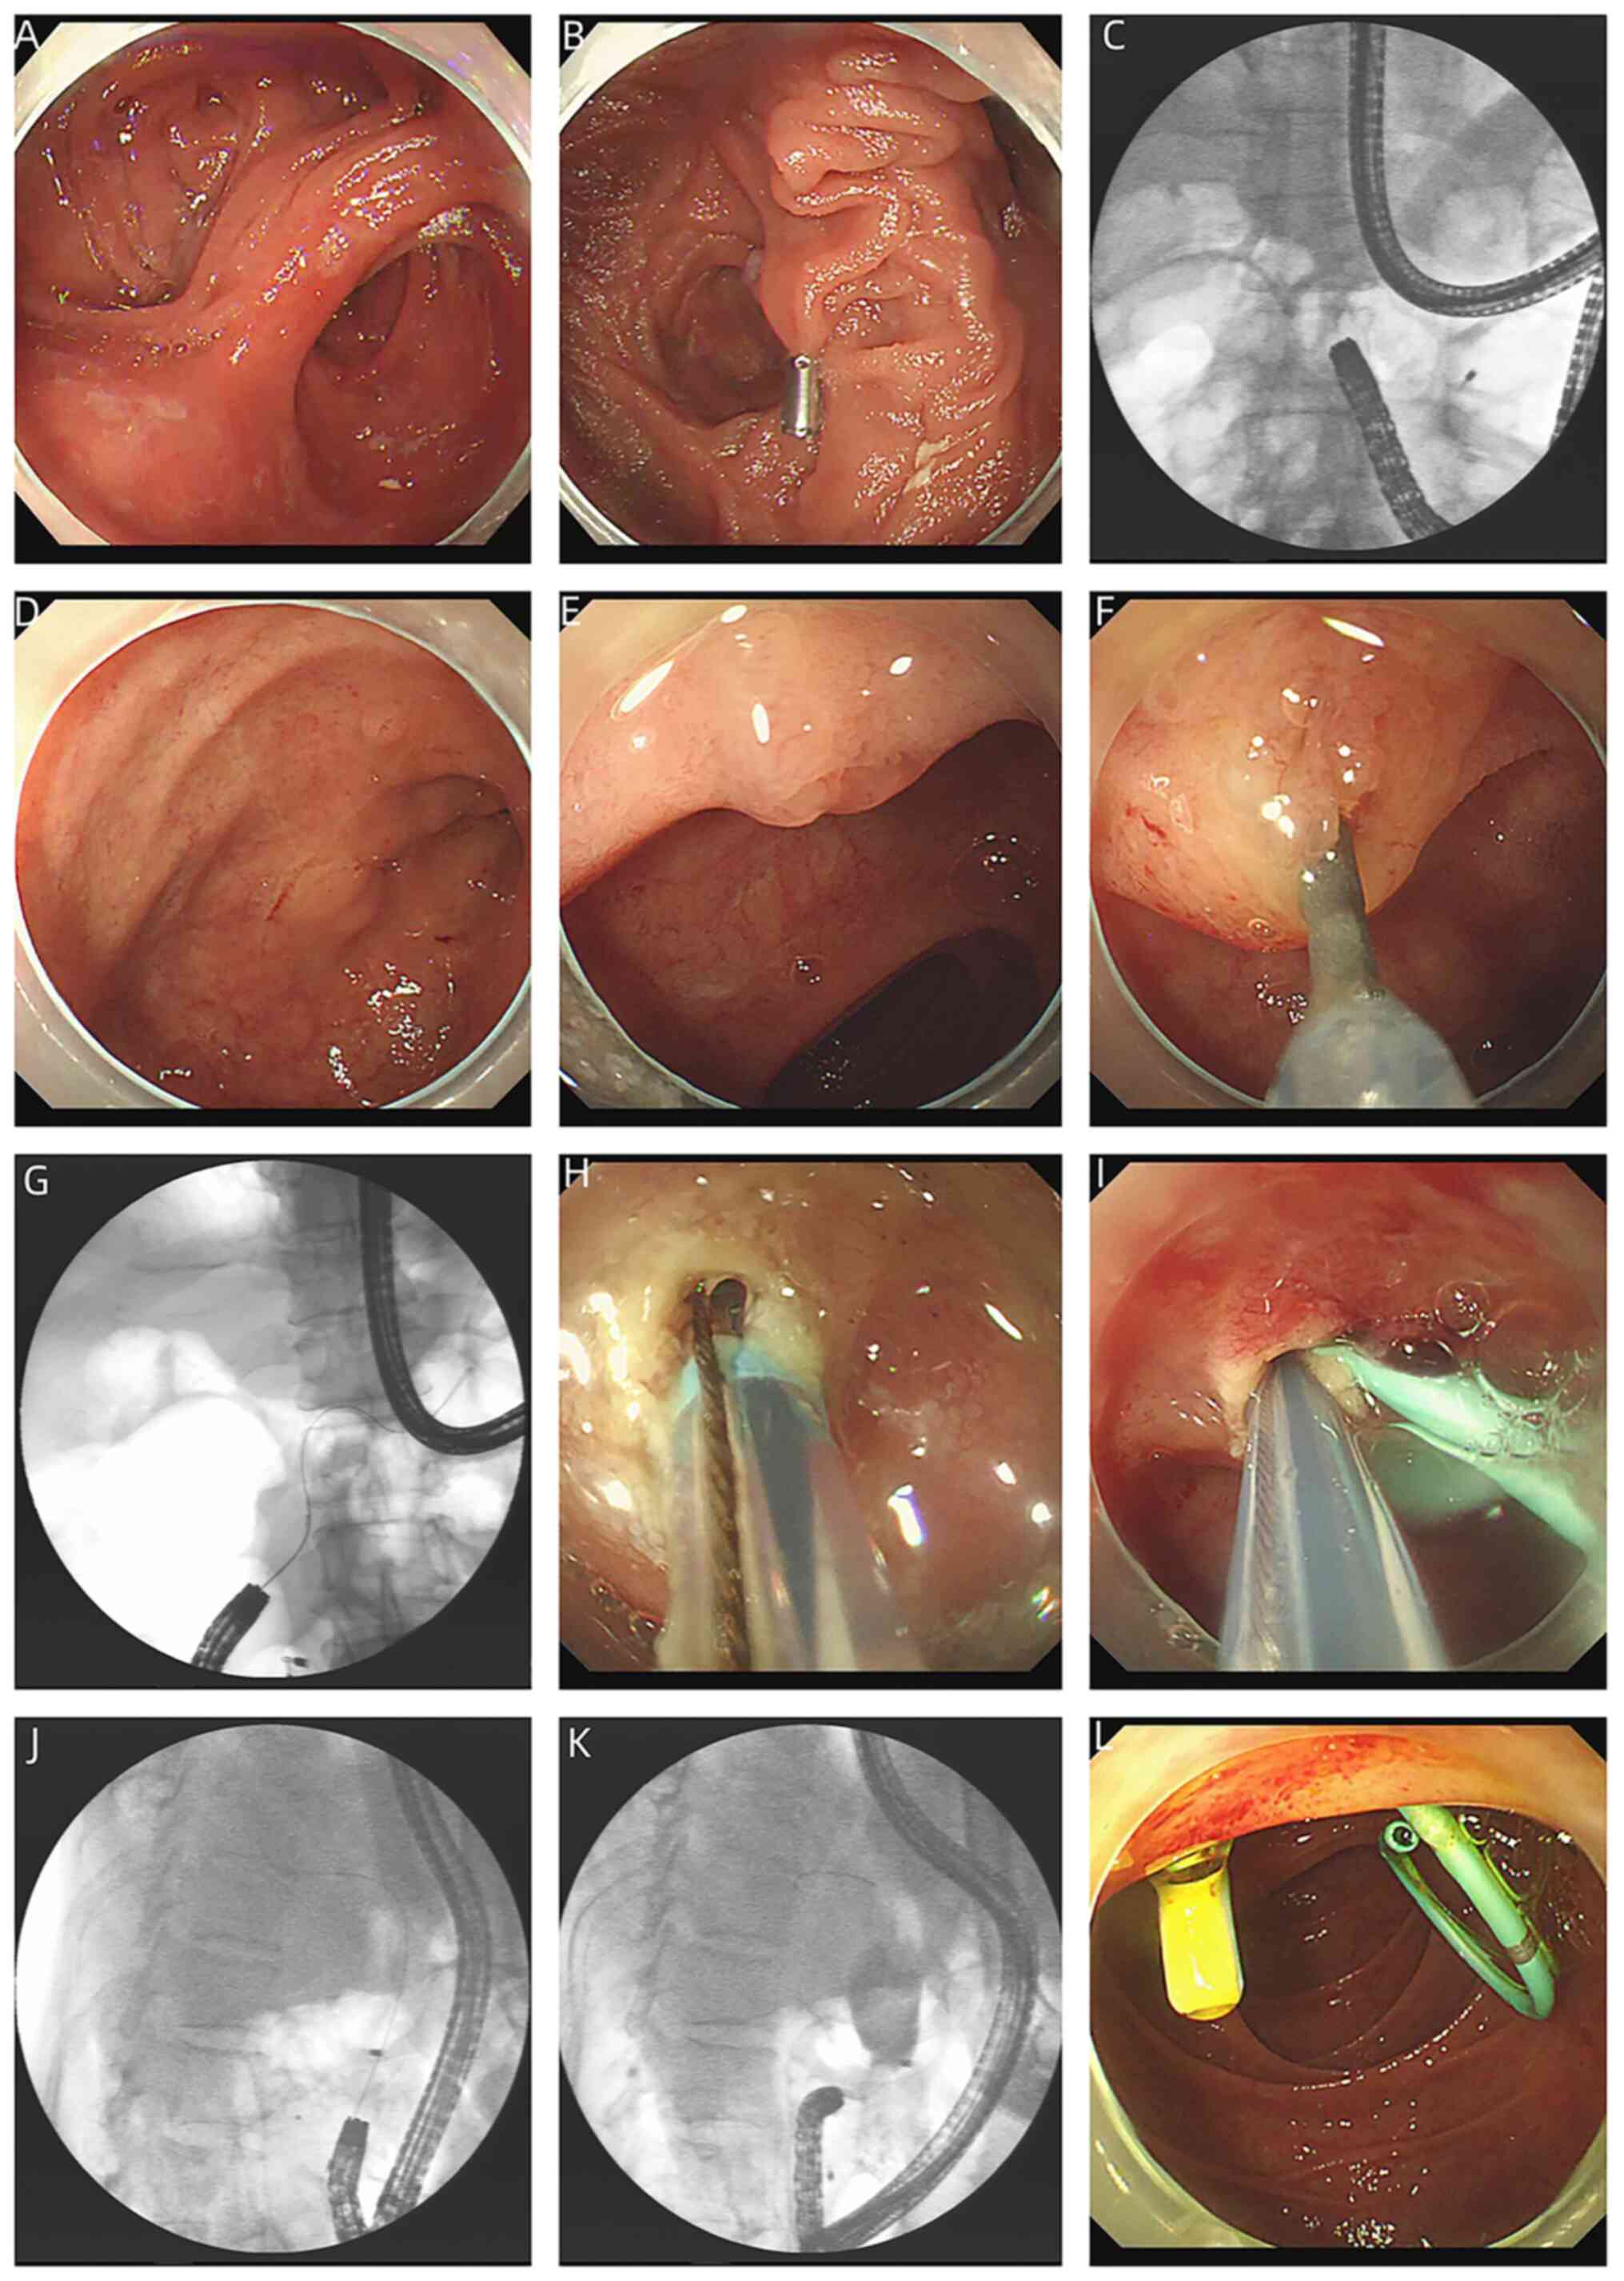

The procedure of ERCP using a pediatric colonoscope in total gastrectomy with Roux-en-Y reconstruction is shown in Fig. 1.

Figure 1

Procedure of endoscopic retrograde cholangiopancreatography using a pediatric colonoscope in a total gastrectomy with Roux-en-Y reconstruction. (A) Esophagojejunal anastomosis. (B) Roux-en-Y anastomosis (using a clip fixed to the mucosa of one limb as a marker). (C) Fluoroscopy (supine position) showing the pediatric endoscope moving to the right upper abdomen. (D) Blind end of the afferent limb. (E) Major papilla. (F) Locating the papilla directly, and making the bile duct axis parallel to the line of sight. (G) Cannulation of the pancreatic duct (supine position). (H) Performing minor endoscopic sphincterotomy in the 11 to 12 o'clock position of the major duodenal papilla. (I) The bile duct was cannulated using the double-guidewire technique and a pancreatic stent was inserted by the first guidewire. (J) Fluoroscopy (left lateral position) confirmed that the bile duct was cannulated. (K) Cholangiography (left lateral position) revealed a large stone in the common bile duct. (L) A biliary plastic stent was inserted.